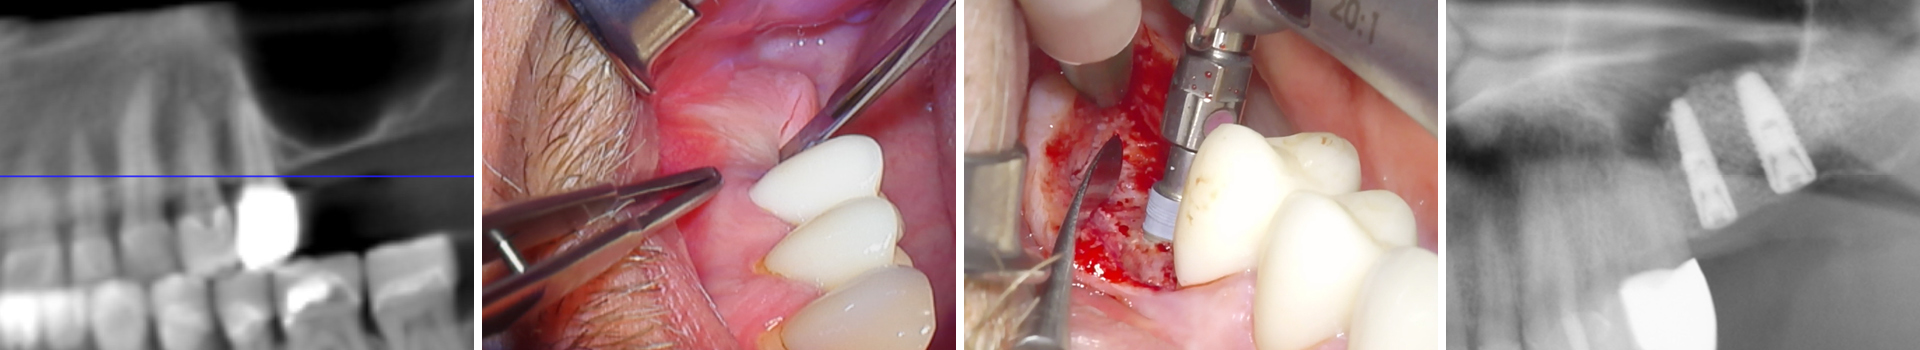

Sinusbodenaugmentation mit xenogenem Augmentationsmaterial und spezieller Kondensationstechnik für eine stabile Implantatinsertion

Der Fall zeigt, wie auch bei ausgedehntem Knochenverlust im Oberkiefer-Seitenzahnbereich mit minimalen Restknochenhöhen des Kieferhöhlenbodens mit Hilfe eines xenogenen Augmentationsmaterials (Apatos Mix, Technos) eine sichere und stabile Sinusbodenaugmentation gelingt.

Der Wunsch des Patienten war eine festsitzende Versorgung der seit längerer Zeit zahnlosen Regionen 26 und 27. Zunächst wurde der Knochen in Volumen und Stabilität für eine folgende Implantation aufgebaut. Nach 6 monatiger Einheilzeit erfolgte die stabile Insertion von 2 Titanimplantaten. Durch eine spezielle Knochenkondensationstechnik (Versah Densah Burs) konnte beim Inserieren der Implantate eine hohe Primärstabilität von 35 Ncm erreicht werden - dies gelingt mit der Methode auch bei Implantaten, die - wie in diesem Fall - zu 80 % im neu aufgebauten Knochen stehen. Die Implantate befinden sich in der Einheilphase, die mit 4 Monaten definiert wurde.

Abbildung 1

OPG Ausgangsbild (Ausschnitt).

Abbildung 2

Zugangsschnittführung zur Kieferhöhle.

Abbildung 3

Sinusbodenaugementation mit xenogenem Material (Apatos Mix; 10 % Eigenknochen aus Zugangspräparation beigemischt).

Abbildung 4

DVT vor Implantation (Ausschitt).

Abbildung 5

Implantatbettaufbereitung mit der Bone Condensing Methode (Versah Densah Burs).

Abbildung 6

Implantinsertion in den augmentierten Bereich.

Abbildung 7

Primärstabilität bei 35 Ncm.

Abbildung 8

OPG nach Implantinsertion (Ausschitt).